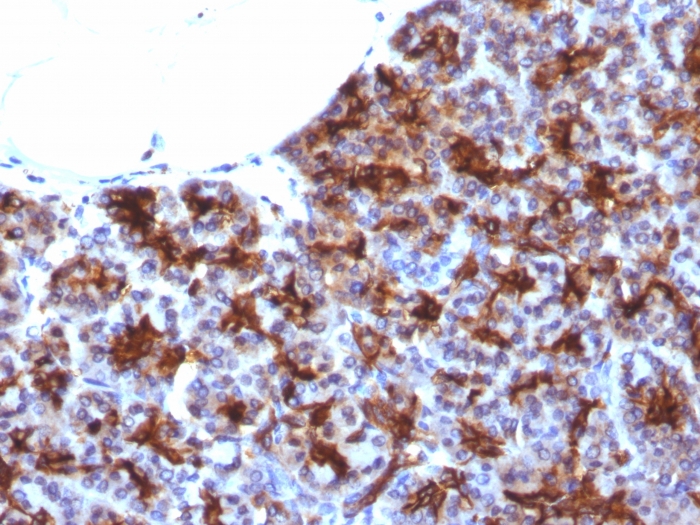

Formalin-fixed, paraffin-embedded human Pancreas stained with MAML3 Monoclonal Antibody (MAML3/1303).